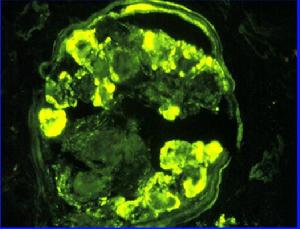

免疫螢光腎小球硬化區可見IgM和C3沉積。

3.免疫螢光檢查在硬化或壞死區可發現C3或IgM及C1q呈不規則、顆粒狀或結節狀分布。無病變的腎小球呈陰性。偶爾系膜區有IgM及C3分布,IgG、IgA少見。